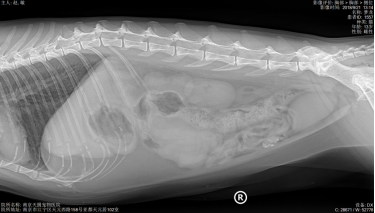

X光显示肺纹理增粗,其他未见异常。

主人叙述2年前体检时,B超检查查出腹腔肿物(直径约6.1CM,场回声团块 ),主人当时选择保守治疗。每天吃完就吐,频繁的呕吐(3-4),导致梦龙体重急剧下降,主人十分担心。到我院初步诊断发现腹部触诊敏感,前腹部大肿物明显,为了准确评估梦龙的情况,医生对梦龙做了X光、生化和B超检查,进一步了解梦龙的身体情况。